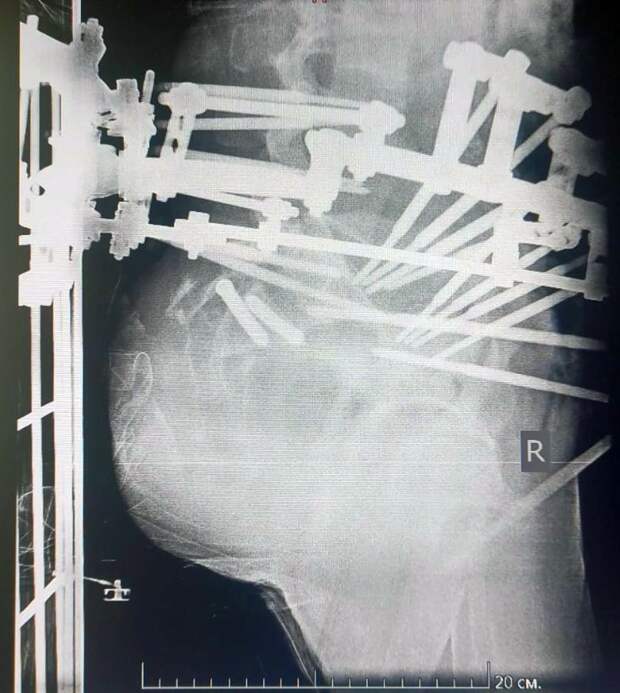

С множественными травмами пациента сначала доставили в Областную больницу № 3 г. Тобольска. Кости таза были настолько разрушены, что, по сути, таз был «оторван» от позвоночника. Врачи компенсировали состояние, выполнили первичную стабилизацию костей аппаратами внешней фиксации.

«Нами была проведена реконструкция повреждений тазового кольца. На первом этапе операции мы выполнили замену аппарата первичной фиксации, наложенного в Тобольске, далее осуществили закрытую репозицию положения костей таза относительно позвоночного столба и его фиксацию в достигнутом положении с помощью специальных тазовых винтов. Следующим этапом операции был домонтаж аппарата таза до кольцевой опоры и соединение его с позвоночником. Таким образом «привязали» таз к позвоночному столбу», — объяснил руководитель Клиники реконструктивной хирургии повреждений конечностей и таза Центра Илизарова, к. м. н. Алексей Гринь.

В перспективе планируется возможная замена внешней фиксирующей конструкции на внутреннюю.